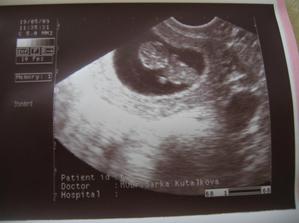

Naše maličké